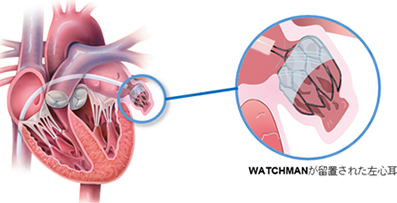

カテーテル的左心耳閉鎖術(WATCHMAN™)

心房細動があると脳梗塞のリスクが高まります。そのため抗凝固薬(血液サラサラ)服用の必要がありますが、それにより出血のリスクも高まります。つまり抗凝固薬による出血リスクが高く(胃や腸からの出血、脳出血、眼底出血を起こしたことがある方なども含む)心房細動がある方が治療対象となります。WATCHMAN™は心房内の左心耳に装置を留置し、心房内で血栓が形成されるのを防ぐ役割を果たします。1回の手技で生涯の脳卒中リスクを低減することが可能です。